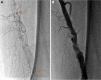

Late formation of pseudoaneurysm related to stent fracture is rarely described in the literature. We describe a case of spontaneous 8-cm femoral superficial artery pseudoaneurysm rupture that had developed from fracture of a stent implanted 3 years previously. Surgical repair was performed with fractured stent removal and reverse saphenous vein bypass.